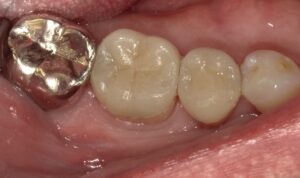

完成されたオーバーレイです。

オーバーレイが装着されたところです。